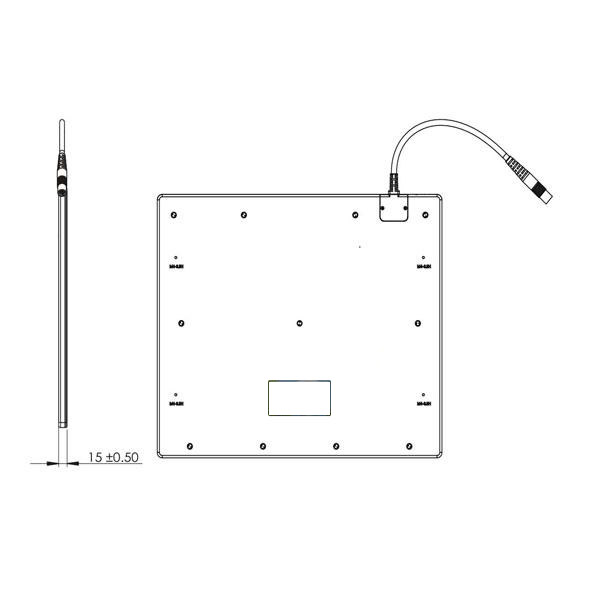

Detector de radiografía multipropósito B.S.D.500L en venta  Características del detector de radiografía multipropósito B.S.D. B.S.D.1500L El detector multipropósito 1500L de 14″ X 17″ (384 460 15 mm³) está diseñado para cumplir con una amplia gama de requisitos para aplicaciones de radiografía digital, por ejemplo, modernización de sistemas de radiografía existentes (p. ej., CCD-DR, CR y película), integración con sistemas de montaje fijo y también varios sistemas DR móviles y portátiles. La tecnología más avanzada de deposición directa de CsI garantiza una excelente calidad de imagen con bajas dosis de rayos X y mejora la seguridad operativa. Sus múltiples modos de sincronización ofrecen flexibilidad universal para fabricantes e integradores de sistemas. El exclusivo detector F²AED™ (Detector Automático de Exposición de Campo Completo) Detectoe ofrece una cobertura completa del área de imagen y una baja sensibilidad a la dosis para un funcionamiento fiable en situaciones difíciles. Su bajo consumo de energía, su diseño de eficiencia térmica y la conexión con un solo cable facilitan la instalación y el funcionamiento del B.S.D.1500L. B.S.D.1500L combina a la perfección un rendimiento robusto y una excelente relación calidad-precio.

Características del detector de radiografía multipropósito B.S.D. B.S.D.1500L El detector multipropósito 1500L de 14″ X 17″ (384 460 15 mm³) está diseñado para cumplir con una amplia gama de requisitos para aplicaciones de radiografía digital, por ejemplo, modernización de sistemas de radiografía existentes (p. ej., CCD-DR, CR y película), integración con sistemas de montaje fijo y también varios sistemas DR móviles y portátiles. La tecnología más avanzada de deposición directa de CsI garantiza una excelente calidad de imagen con bajas dosis de rayos X y mejora la seguridad operativa. Sus múltiples modos de sincronización ofrecen flexibilidad universal para fabricantes e integradores de sistemas. El exclusivo detector F²AED™ (Detector Automático de Exposición de Campo Completo) Detectoe ofrece una cobertura completa del área de imagen y una baja sensibilidad a la dosis para un funcionamiento fiable en situaciones difíciles. Su bajo consumo de energía, su diseño de eficiencia térmica y la conexión con un solo cable facilitan la instalación y el funcionamiento del B.S.D.1500L. B.S.D.1500L combina a la perfección un rendimiento robusto y una excelente relación calidad-precio.

El mejor detector de radiografía multipropósito B.S.D.1500L Especificaciones Sensor Centelleador Depósito directo de CsI Área activa 434 x 355 mm² (14″x17″) Matriz de píxeles 2816X2304 Paso de píxeles 154 μm Calidad de imagen Resolución límite 3,3 lp/mm MTF >70 %……(@1 lp/mm) >40 %……(@2 lp/mm) >22 %……(@3 lp/mm) DQE >65 %……(@0 lp/mm) >20 %……(@3 lp/mm) Sensibilidad ~0,62 ct/nGy Dosis lineal máxima 95 Gy Rango dinámico >82 dB Escala de grises 16 bits Interfaz de comunicación Interfaz de comunicación Gigabit Ethernet Tiempo de adquisición de imágenes 2-3 s Control de exposición F²AED™ Manual Ambiental Funcionamiento Enfriamiento natural Rango de temperatura 5 ℃-35 ℃ (41 ℉-95 ℉) Rango de humedad (sin condensación) 30 %-75 % HR Rango de temperatura de almacenamiento -20 ℃-55 ℃ (-4 ℉-67 ℉) Rango de humedad 10 %-90 % HR Mecánico Dimensiones 384 x 460 x 15 mm3 (15″ x 18″ x 0,6″) Peso 3,4 kg Material de la carcasa Parte frontal de fibra de carbono Parte trasera de aleación de aluminio de alta resistencia Potencia Disipación de potencia 8 W (en espera) 20 W (en funcionamiento) Fuente de alimentación 100-240 V CA Frecuencia 50/60 Hz Regulador FDA *(En progreso) CE HD60077005 0001 UL E464810

El mejor detector de radiografía multipropósito B.S.D.1500L Especificaciones Sensor Centelleador Depósito directo de CsI Área activa 434 x 355 mm² (14″x17″) Matriz de píxeles 2816X2304 Paso de píxeles 154 μm Calidad de imagen Resolución límite 3,3 lp/mm MTF >70 %……(@1 lp/mm) >40 %……(@2 lp/mm) >22 %……(@3 lp/mm) DQE >65 %……(@0 lp/mm) >20 %……(@3 lp/mm) Sensibilidad ~0,62 ct/nGy Dosis lineal máxima 95 Gy Rango dinámico >82 dB Escala de grises 16 bits Interfaz de comunicación Interfaz de comunicación Gigabit Ethernet Tiempo de adquisición de imágenes 2-3 s Control de exposición F²AED™ Manual Ambiental Funcionamiento Enfriamiento natural Rango de temperatura 5 ℃-35 ℃ (41 ℉-95 ℉) Rango de humedad (sin condensación) 30 %-75 % HR Rango de temperatura de almacenamiento -20 ℃-55 ℃ (-4 ℉-67 ℉) Rango de humedad 10 %-90 % HR Mecánico Dimensiones 384 x 460 x 15 mm3 (15″ x 18″ x 0,6″) Peso 3,4 kg Material de la carcasa Parte frontal de fibra de carbono Parte trasera de aleación de aluminio de alta resistencia Potencia Disipación de potencia 8 W (en espera) 20 W (en funcionamiento) Fuente de alimentación 100-240 V CA Frecuencia 50/60 Hz Regulador FDA *(En progreso) CE HD60077005 0001 UL E464810